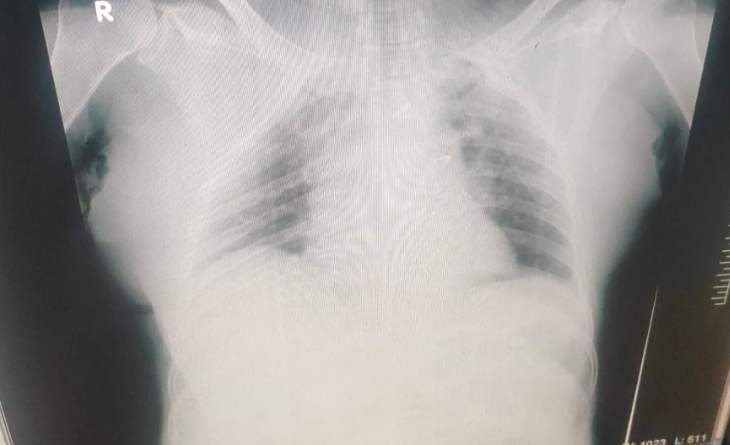

CHEST X-RAY AP VIEW